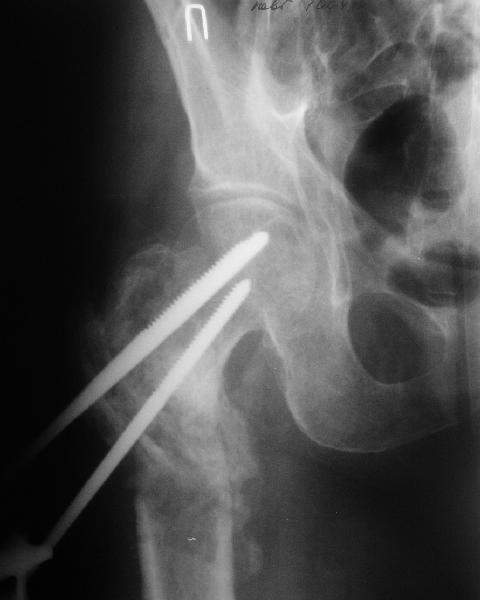

Возможно, пример (в приложении) поможет Вам определиться с выбором тактики лечения (у нашего пациента, кроме тугого ложного сустава вертельной области, сложная деформация н/3 бедренной кости; т.к. это не имеет значения к обсуждаемой теме - оставил "за кадром"). Как Вы видите, мы в данном случае не вводили чрескостные элементы в зону установки имплантата. При отказе от наложения опоры на таз (кстати, она не обязательно может быть громоздкая спицевая; арки со стержнями-шурупами, введенными в крыло подвздошной вполне достаточно) "не удивляйтесь", если опора со стержнями-шурупами, введенными в вертельной области в скором времени дестабилизируется, возникнет воспаление мягких тканей у чрескостных элементов. Такая опора "имеет на это право": нагрузка конечности от вершины дистального фрагмента до кончиков пальцев ляжет на нее. А двух-трех введенных рядом стержней-шурупов, как их не разноси от фронтальной плоскости, в данном

случае явно недостаточно для адекватной фиксации. + для того, чтобы выбрать оптимальные чрескостные элементы для промежуточной и дистальной опор, можете воспользоваться атласом